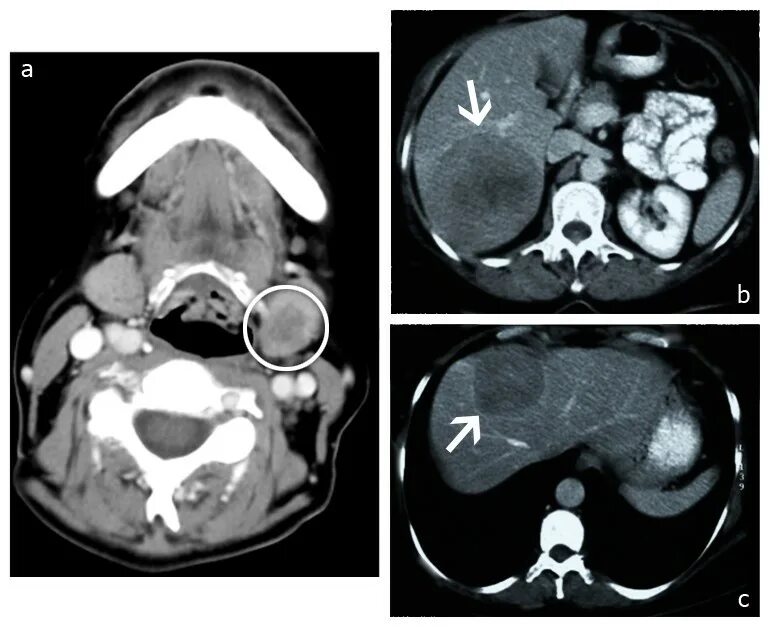

Миндалины на кт